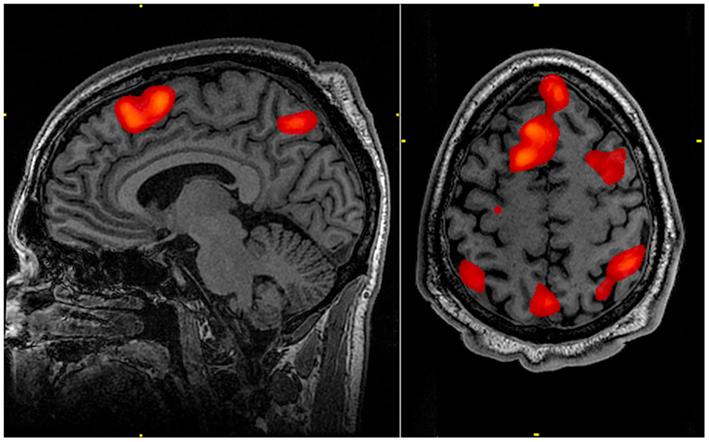

The researchers discovered that some brain waves, called alpha and gamma, changed pattern even after blood had stopped flowing to the brain. “Given that cross-coupling between alpha and gamma activity is involved in cognitive processes and memory recall in healthy subjects, it is intriguing to speculate that such activity could support a last ‘recall of life’ that may take place in the near-death state,” they wrote.

And whether or not we succeed, or have the illusion that we did, this must result in absolute mental bliss. I hope that future research in the field, with longer measurements of neural activity after death, perhaps even brain imaging, will provide support for this idea – whether it lasts for minutes or hours, for the sake of my brother, and that of all of us.